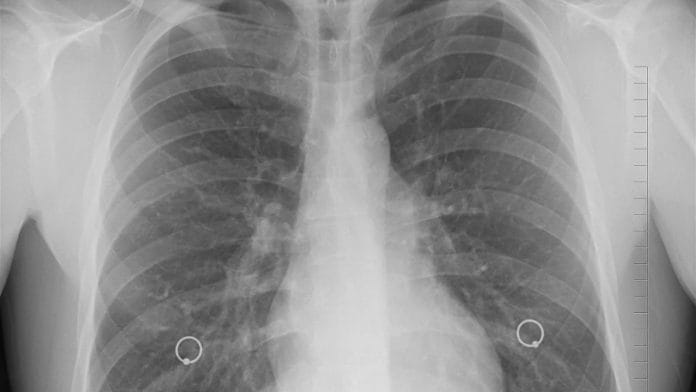

The most common cause of cancer death worldwide is lung cancer, a burden that is most heavily felt in lower- and middle-income countries (LMICs) where early detection and treatment is limited. By understanding the gaps and barriers in identifying and treating lung cancer in LMICs, healthcare systems can invest in the necessary infrastructure to curb cancer trends as populations continue to age.

Lung cancer is an unequal burden

Worldwide, approximately 70% of cancer deaths occur in LMICs, a large fraction of which is attributed to lung cancer. Smoking is the leading risk factor for lung cancer and over 80% of smokers worldwide live in LMICs.

Environmental factors like poor air conditions created by traffic and residential heating also contribute to this disease. Smoking habits, industrialized cities, and growing populations, raise the need for widespread cancer screening across LMICs for early detection and treatment.

Early detection of cancer is one of the most effective ways to improve survival outcomes. Detection begins with screening to identify individuals with cancerous or pre-cancerous abnormalities. Next, diagnosis helps determine the most effective treatment regimen, which can save time and resources.

Infrastructure challenges like a lack of transportation, long travel distances, and poor road conditions can limit access to cancer screening in LMICs. The equipment and personnel necessary also means that available screening centres may be limited. Lung cancer symptoms that are similar to other diseases like tuberculosis, which infects the lungs, can lead to misdiagnoses and further delay treatment.